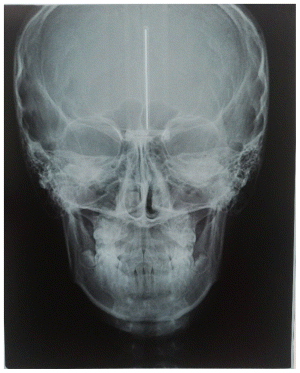

The patient was a young female presenting with a Class III dento-skeletal malocclusion, which was treated using the AMCOP® TC appliance. A comprehensive diagnostic protocol was carried out both before and after treatment, including orthopantomography (Figure 2–3), postero-anterior teleradiography (Figures 4, 5), latero-lateral cephalometric radiography (Figures 6, 7), cephalometric analysis (Tables 1, 2), as well as extraoral (Figures 8, 9) and intraoral photographs (Figures 10, 11). The extraoral examination revealed an edge-to-edge incisal relationship and the presence of a midline diastema. Pre-treatment cephalometric analysis (Deltadent® Lana, Bolzano, Italy) confirmed the diagnosis of a skeletal Class III malocclusion. The treatment plan involved the use of the AMCOP® TC appliance. The patient was instructed to wear the device for two hours in the afternoon and throughout the night for the first six months, followed by nighttime use only for an additional six months. Upon completion of the treatment, the patient achieved a Class I occlusion, with correction of both overjet and overbite. Additionally, the device facilitated tongue re-education and contributed to the postural realignment of the first cervical vertebra.